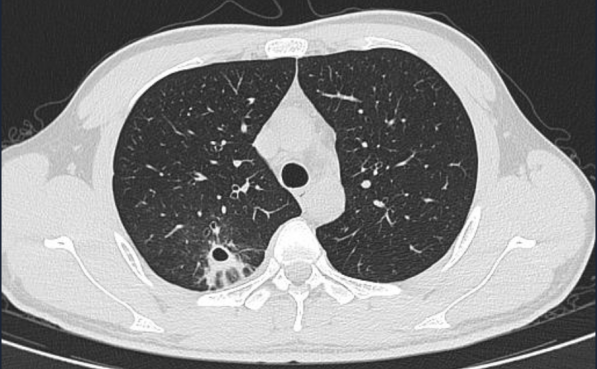

· 病例概况26岁青年男性,工作繁忙、压力大、熬夜,咳嗽1月余,多次外院抗细菌治疗,咳嗽咳痰症状较前无好转。入院查抗酸染色及抗结核抗体均为阴性,查胸部CT及支气管镜肺泡灌洗病原学tNGS明确诊断肺结核。

△胸部CT示右肺上叶后段炎症,拟脓肿形成

· 发病关联短期免疫力骤降,导致潜伏的结核菌激活,并引发强烈的变态反应。

· 临床特点起病急、进展快,多以发热、咳嗽、脓胸为首发,咳嗽超过2周,止咳效果不佳。